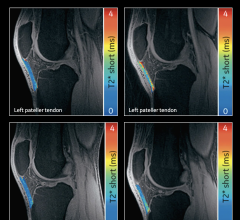

May 12, 2025 — GE HealthCare recently unveiled Signa Sprint, an FDA 510(k) pending[1] ultra-premium wide bore 1.5T high ...